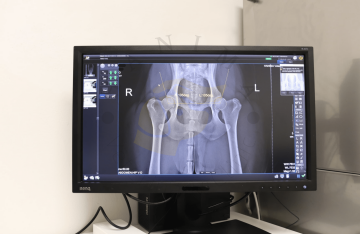

RTG vyšetření skeletu a kloubů

PennHIP screening